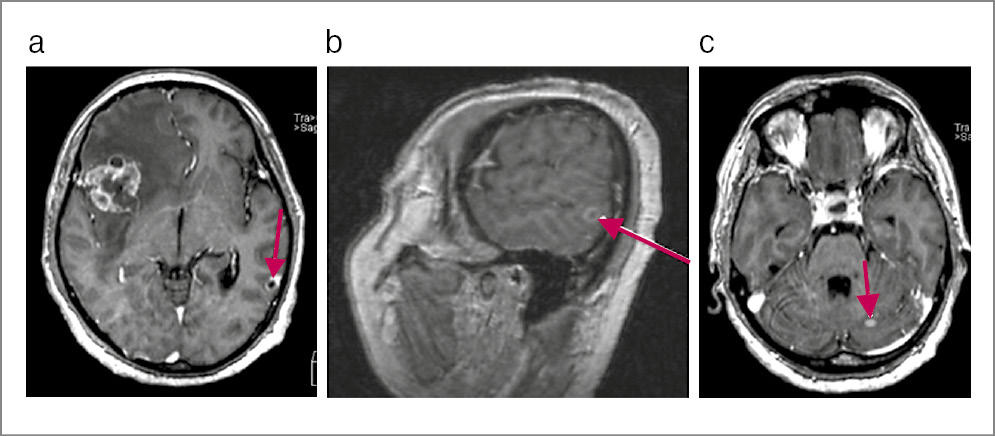

По данным магнитно-резонансной томографии (МРТ) ГМ с контрастированием в островковой доле справа с распространением на лобную и височную визуализируется внутримозговое кистозно-солидное образование с бугристым контуром размером 3,7×3,3×2,9 см. Отмечаются выраженный перифокальный отек с переходом на лобную и височную доли, базальные ядра со смещением срединных структур на 1,3 см. Аналогичные образования выявлены в задних отделах левой височной доли и левом полушарии мозжечка, размеры которых составили 1,1×0,8 и 0,5×0,6 см соответственно. В гипофизе определяется кровоизлияние. Соответственно, у больного имеются объемные образования в правой островковой, левой височной долях и левом полушарии мозжечка с кровоизлиянием в гипофиз (рис. 1, 2).

Рис. 1. Пациент Л., 66 лет. МРТ ГМ. Крупное кистозно-солидное образование вторичного характера в правой островковой доле размером 3,7×3,3×2,9 см, с выраженным перифокальным отеком, приводящим к смещению срединных структур влево (стрелки).

Рис. 2. Больной Л., 66 лет. МРТ ГМ: a, b – кистозно-солидное образование вторичного характера в левой височной доле размером 1,1×0,8 см с выраженным накоплением контраста солидным компонентом; c – контрастпозитивное образование вторичного характера в левой гемисфере мозжечка размером 0,5×0,6 см, которое не определяется на нативных программах (стрелки).